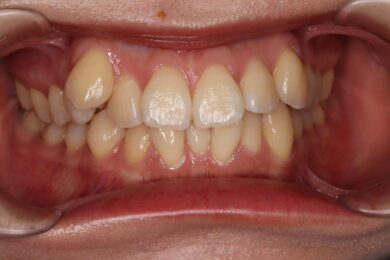

八重歯・叢生 マウスピース矯正(インビザライン)26歳女性 非抜歯

「前歯のガタガタ(叢生)と八重歯を治したい」を主訴に来院された患者様です。上下の歯にIPRを加え、歯列弓の拡大を行い、非抜歯で前歯のガタガタを整えました。顎間ゴムを用い、咬み合わせも改善されています。アライナーの装着時間が長く、チューイをしっかり使用していただけたため、非常に短時間で仕上がりました。

• 治療前